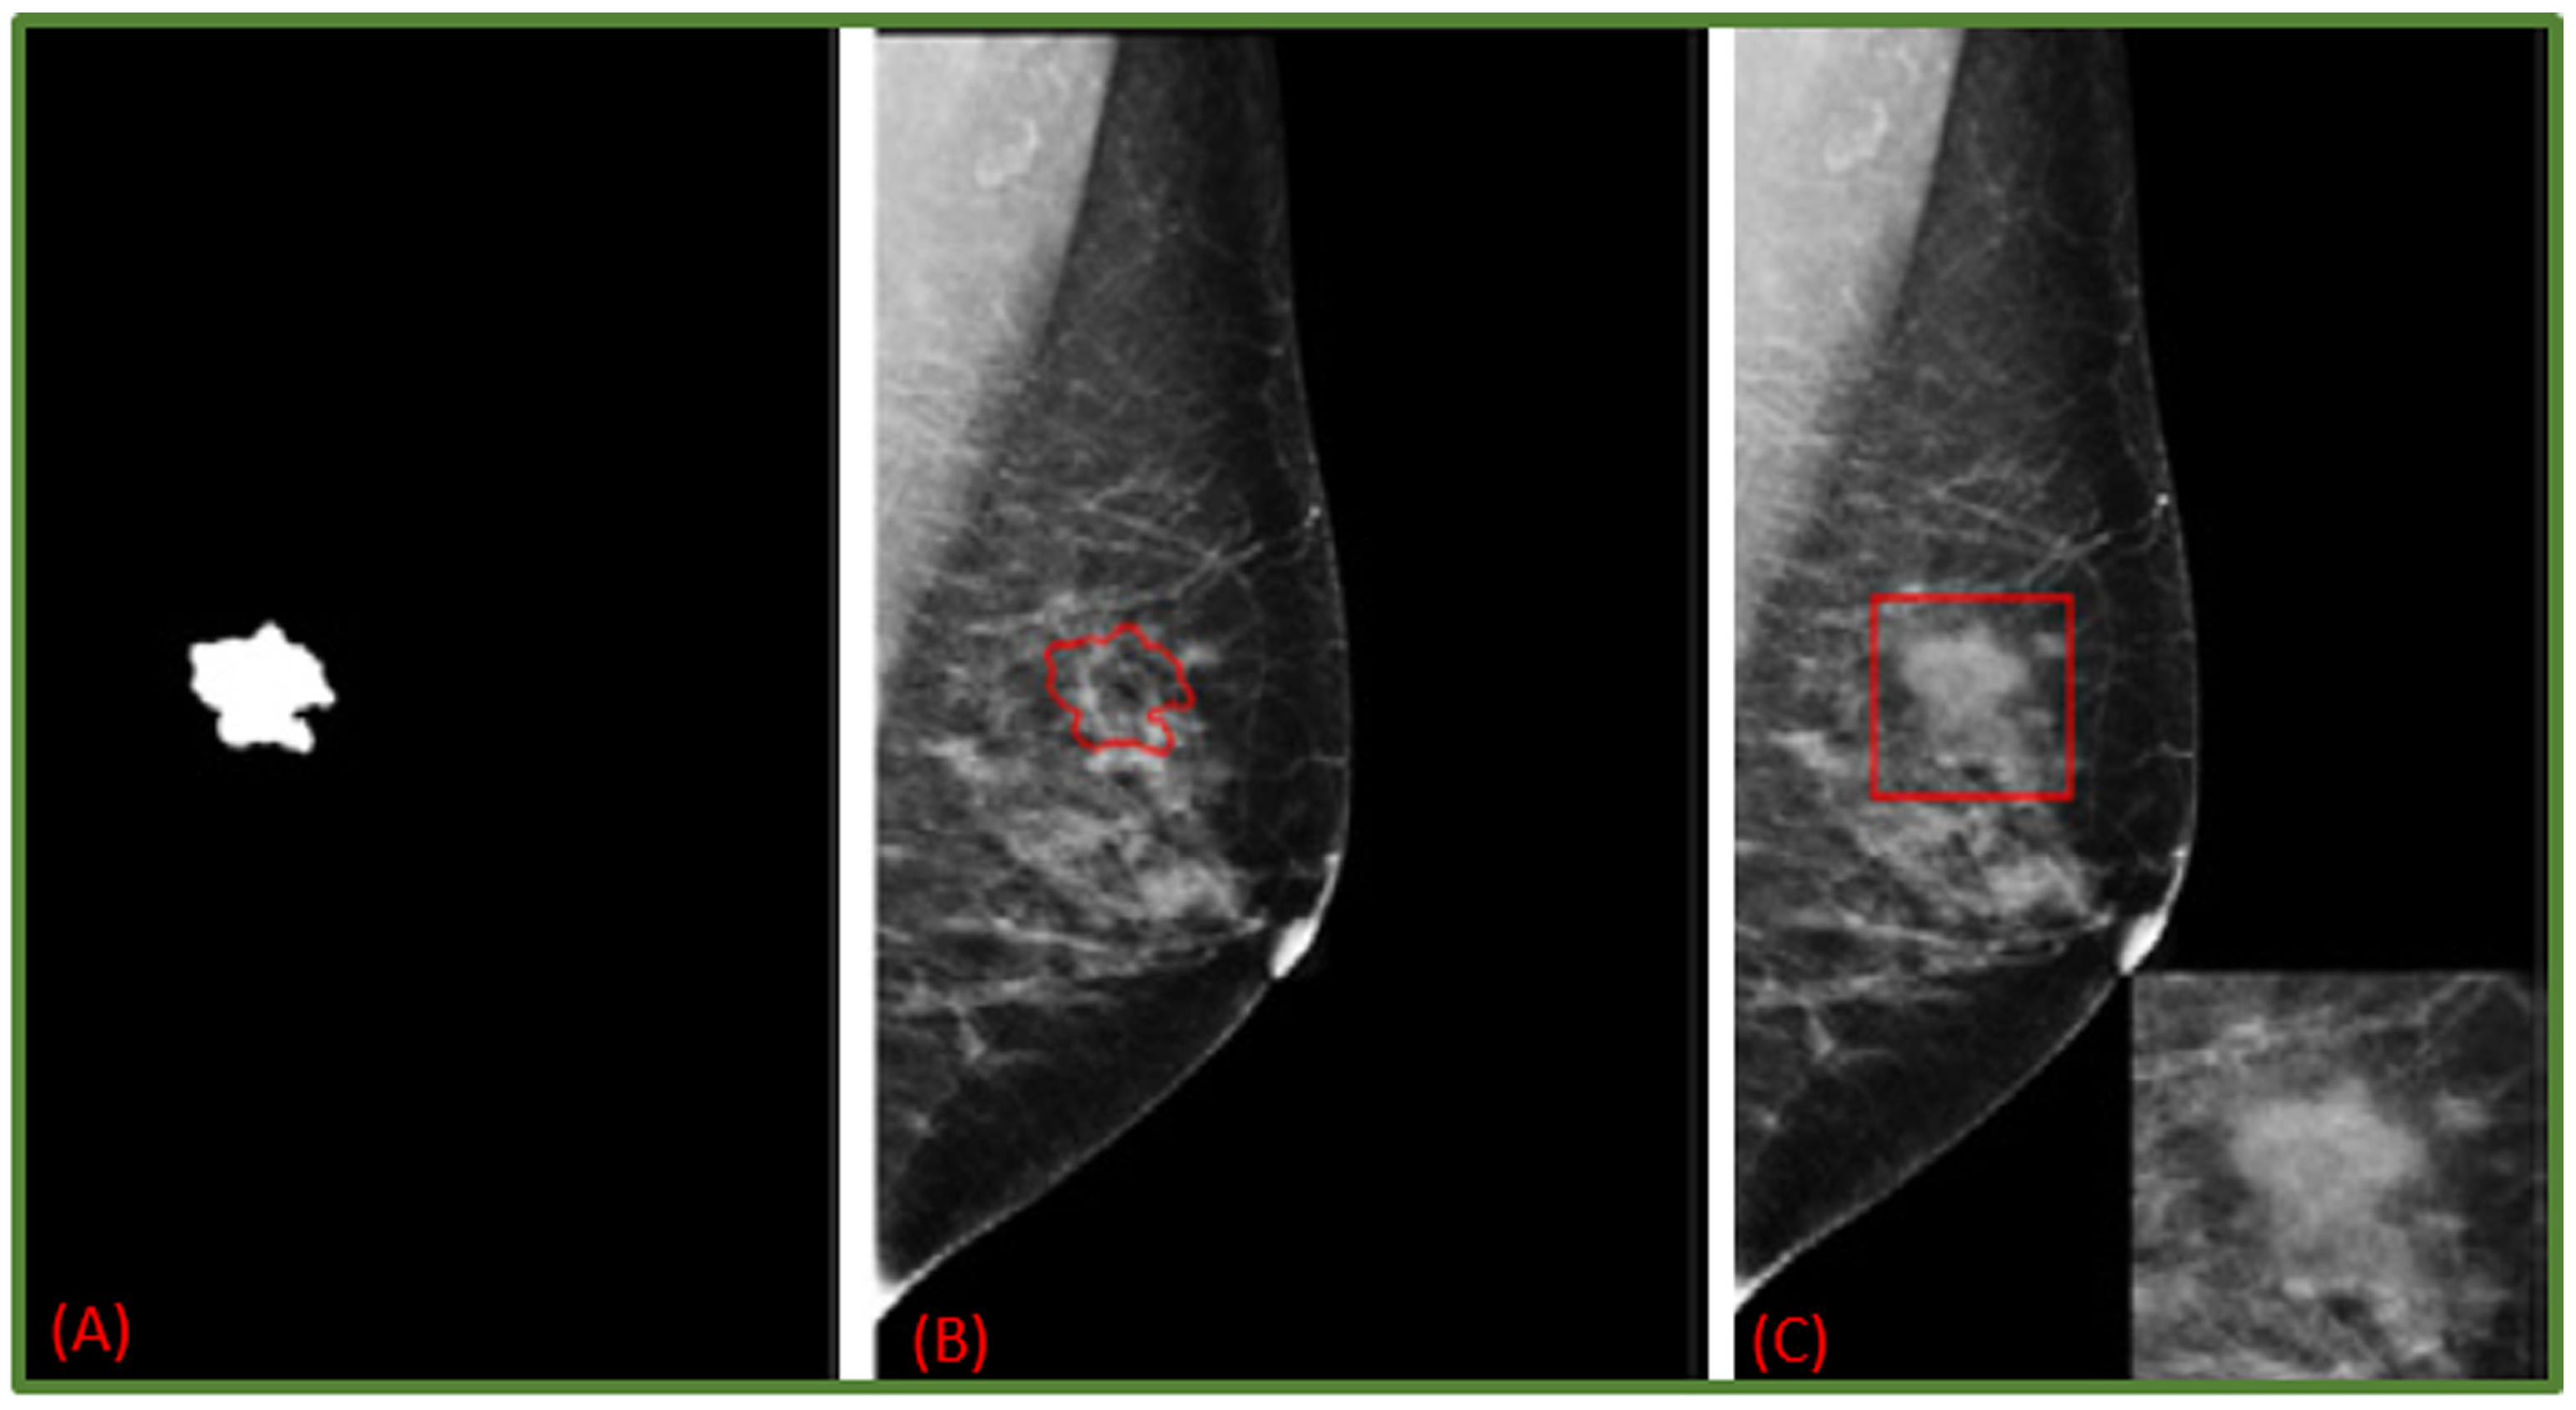

- Costa, A.C.; Oliveira, H.C.; Vieira, M.A. Data augmentation: Effect in deep convolutional neural network for the detection of architectural distortion in digital mammography. In Proceedings of the Brazilian Congress on Medical Physics, Santos, Brazil, 21–24 August 2019. [Google Scholar]

- Zeiser, F.A.; da Costa, C.A.; Zonta, T.; Marques, N.; Roehe, A.V.; Moreno, M.; da Rosa Righi, R. Segmentation of masses on mammograms using data augmentation and deep learning. J. Digit. Imaging 2020, 33, 858–868. [Google Scholar] [CrossRef] [PubMed]